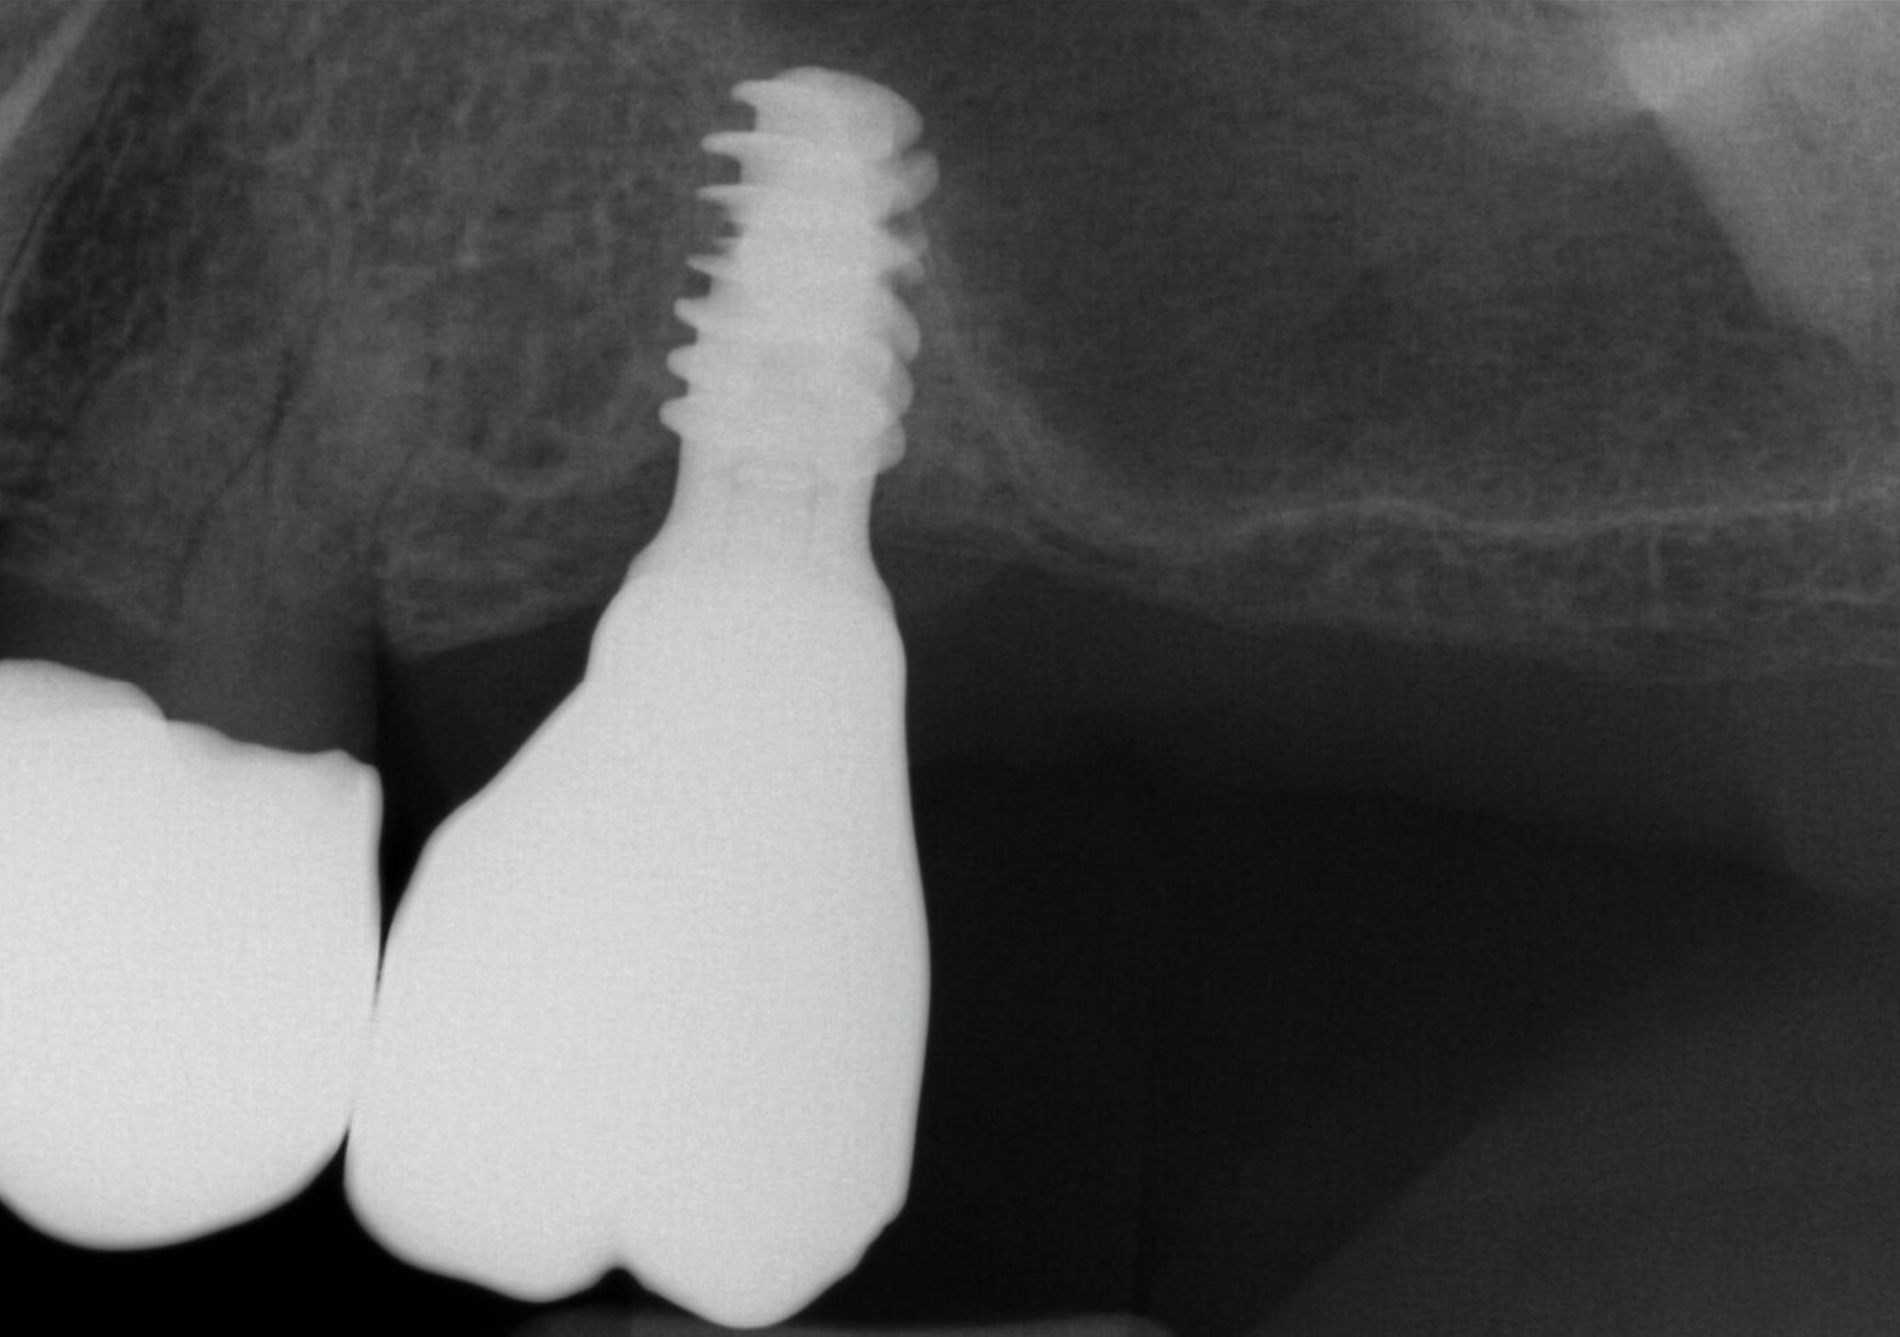

Nach Durchführung einer dentalen Volumentomografie (DVT) wurden daher zahnärztliche Implantate in Regio 14, 15 und 25 im Sinne einer verkürzten Zahnreihe geplant und inseriert (Abbildung 7). Nach dreimonatiger subgingivaler, konventioneller Einheilzeit wurden die Implantate freigelegt. Zwei Wochen später begann man die vorhandenen Primärkronen zu entfernen. Die Stümpfe wurden nachpräpariert und es wurden erneut Fäden gelegt (Abbildung 8a und 8b).

Um den Sitz der Implantatkronen nach dem Einsetzen zu prüfen, wurden intraorale Tubusaufnahmen im Sinne eines Baseline-Röntgens angefertigt (Abbildung 9). In den Folgeterminen wurde dem Patienten noch eine Aufbissschiene für den Oberkiefer eingegliedert, um etwaigem nächtlichen Bruxismus vorzubeugen. Für die Nachsorge empfiehlt sich ein halbjährliches Kontrollintervall.